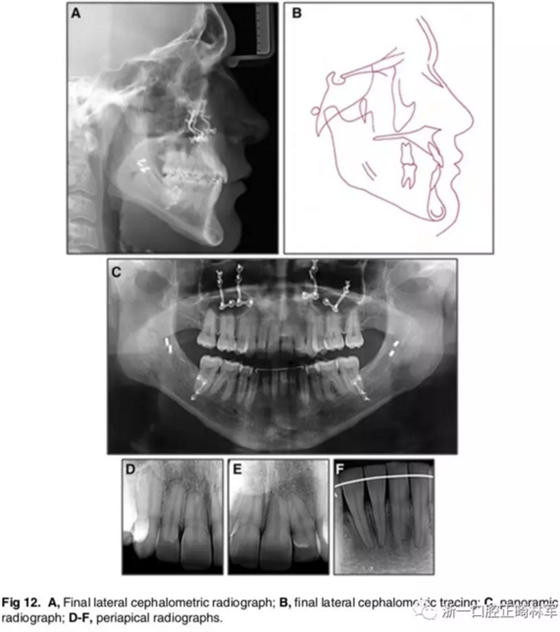

影像學(xué):全景片示:牙根平行度可。頭顱側(cè)位片及疊加圖示:顯著的骨性、牙性改變;其中,最大的改變?yōu)樯舷骂M位置關(guān)系,改變了7mm;由此帶來的改變?yōu)锳NB角從-4°變?yōu)?°,Wits值由-10mm變?yōu)?1.5mm,上頜突度減?。ˋ-NPer,3mm),上下頜不調(diào)改善(Co-A-Co-Gn,41mm),從而使側(cè)貌更為平直;下頜磨牙遠(yuǎn)中移動,無伸長、傾斜,反映了下頜整體的遠(yuǎn)中移動;上下切牙傾角糾正(1:NA,7mm、25°; 1:NB,4.5mm、20°; IMPA,78°),從而改善了在基骨中的位置。

功能:前伸合的切牙引導(dǎo)與側(cè)方合的尖牙引導(dǎo)得以實(shí)現(xiàn)。

側(cè)貌:上唇突度增大4mm(至S線0mm),整體側(cè)貌更為和諧。

5年隨訪:治療結(jié)果保持穩(wěn)定,無明顯復(fù)發(fā),但下頜中線有輕微偏移;下頜磨牙位置始終保持穩(wěn)定。